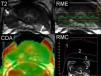

RM de difusiónLos avances tecnológicos de la RM han permitido una expansión en la utilización de la secuencia de difusión (RMD) en otros órganos más allá de su aplicación inicial en el infarto cerebral. La secuencia de difusión aporta información acerca del movimiento browniano aleatorio de las moléculas de agua libre en el espacio intersticial y a través de la membrana celular. En general el tejido neoplásico tiene más restricción de la difusión que el tejido normal debido a la mayor densidad celular, que dificulta la normal difusión de las moléculas de agua22. La secuencia de difusión aporta información, aparte de la densidad celular, de la tortuosidad del espacio extracelular, la integridad de las membranas celulares y el grado de organización glandular. En nuestro equipo la secuencia de difusión es eco planar espín eco (tabla 1) (spin echo—single shot echo planar image) (TR/TE: 6.000–6.500/mínimo ms, factor b: 0 y 1.000s/mm2 en el plano axial). La planificación de la secuencia de difusión debe incluir toda la pelvis además de la próstata y las vesículas seminales para poder realizar al mismo tiempo la estadificación regional y detectar una posible lesión glandular prostática en la misma secuencia de adquisición. La baja movilidad de las moléculas se refleja como una alta señal en las imágenes en RMD y, por el contrario, las moléculas que tienen gran movilidad mostrarán una pérdida de señal. La interpretación de la secuencia requiere realizar el procesado y cuantificar la difusión mediante el CDA (coeficiente de difusión aparente) en el mapa paramétrico (fig. 5). La cuantificación se realiza colocando el área de interés (ROI) de 5–10mm2 sobre la región a considerar. El valor del factor b a utilizar es variable sin que exista consenso23. De todas formas se recomiendan valores=0 y ≥1.000s/mm2 en la próstata. La utilización de valores de factor b más elevados condiciona una mayor sensibilidad de la secuencia, al eliminar la hiperseñal de los tejidos con tiempo de relajación T2 más largos (edema o fluido debido a su alta densidad de protones), fenómeno denominado «T2 shine-through». Las lesiones con verdadera restricción de la difusión aparecerán con baja señal en el mapa de CDA de escala de grises o azules en el mapa en color (fig. 5). No existe un valor de CDA claro que distinga entre cáncer y ausencia de cáncer, aunque cifras <1,2×10−3mm2/s representan un umbral bastante indicativo de un proceso neoplásico24. Para evitar errores de interpretación de las imágenes de difusión resulta necesario valorarlas conjuntamente con las imágenes anatómicas. Las ventajas de la difusión son el tiempo de adquisición corto y la buena resolución del contraste entre el tumor y el tejido normal. Los inconvenientes son la escasa resolución espacial y los posibles artefactos de susceptibilidad por hemorragia postbiopsia (tabla 2).

Cáncer de próstata central. Lesión focal hipointensa en la zona central izquierda en el corte axial en T2. La secuencia de RME muestra elevación del pico de la colina (flecha). La secuencia de RMD muestra leve hiperintensidad inespecífica (flecha). El mapa paramétrico CDA en color muestra valores bajos de CDA en el nivel lesional traducido por color azul (flecha), pudiendo cuantificar el valor CDA colocando la región de interés (ROI).